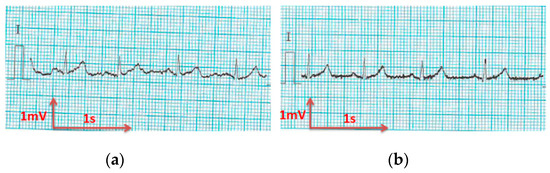

3.3.2. ECG Recorded by Low-Cost Arduino Based Open Source

- For all textile electrodes, ECG signals were recorded by a portable medical device as well as with a low-cost, Arduino-based open source device. Using portable medical devices, all electrocardiographic P, T waves, and QRS complexes were identifiable, despite higher contact impedance of PEDOT:PSS textile electrodes. Signal quality analysis by cardiologist showed that these textile electrodes, used in ambulatory conditions for heart monitoring, allow the detection of rhythmic disorders (Atrial Fibrillation, ventricular tachycardia, etc.) and conduction troubles (sinus dysfunction, atrioventricular block etc.), and can detect myocardial ischemia (ST segment underlining) in some cases. Such a system, integrated into garments, can be used in real-time and in continuous mode to monitor the user’s heart in a comfortable way, and to detect possible issues that, with additional analysis if needed, could be avoided, such as strokes. Regarding low-cost devices, assuming that high contact impedance between the skin and textile electrodes is the cause of no detectability or noise and severe distortion of cardiac waveforms, it was concluded that the amplifiers of the low-cost device are not appropriate to record ECG of our developed PEDOT:PSS textile electrodes, and also, that of commercial silver-plated electrodes. Textile electrodes inherently provide high contact skin-electrode impedance because the ECG recording is based only on natural skin moisture and perspiration and without any added gel. Therefore, compatible recording amplifiers with high input impedance are required to compensate for the high contact impedance skin-electrode, which is related to the low mobility of ions across the highly-resistant stratum corneum layer of the skin that causes weak conductivity between the electrodes and the skin.